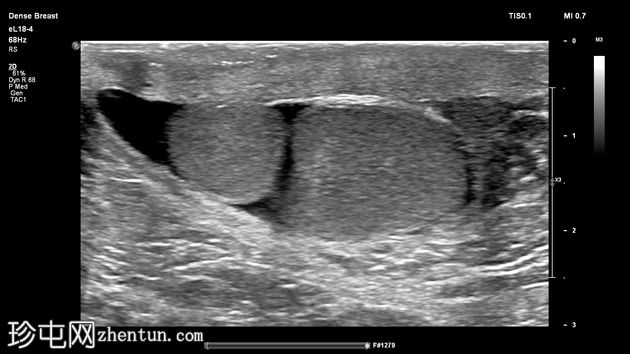

左侧阴囊内可见两个相邻但彼此分离的小睾丸,头侧体积分别为1毫升和3.5毫升,共用一个附睾。

两个睾丸回声和血流均正常,内部未见病变,但患侧可见少量鞘膜积液。

右侧睾丸大小、回声和血流均正常,内部未见病变,体积为4毫升。其附睾正常,未见鞘膜积液。